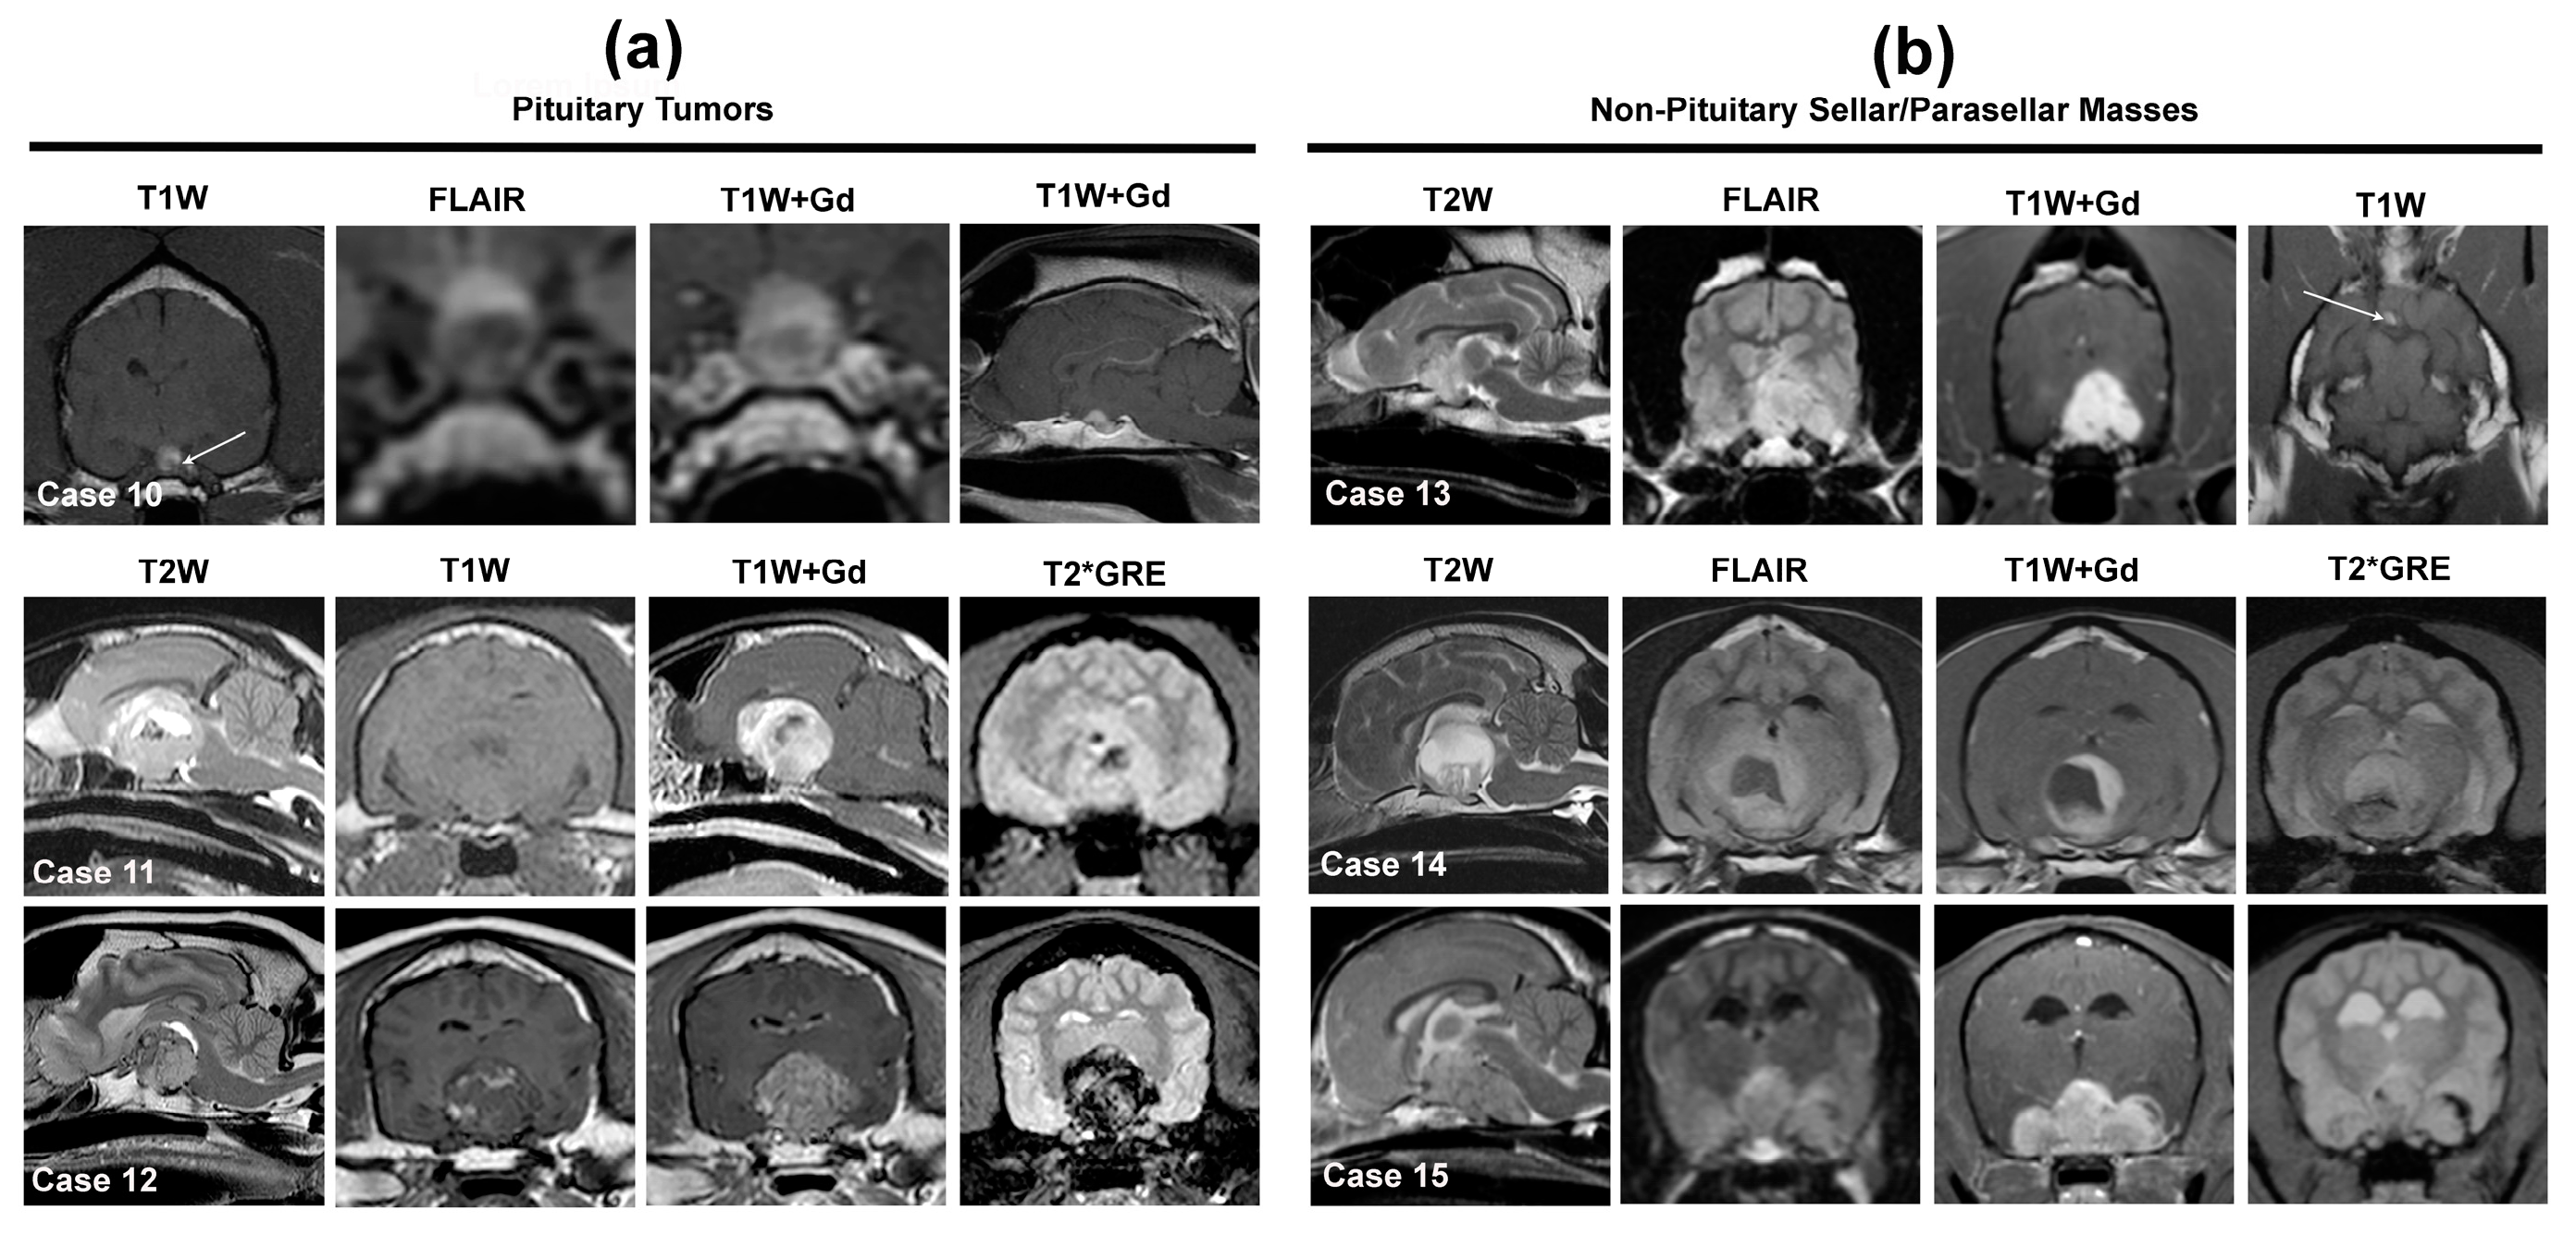

Figure 4.

MRI features of solitary, extra-axial, sellar, and parasellar neoplastic lesions in dogs and cats. Cases 10–12 illustrate pituitary (sellar) tumors (a), and Cases 13–15 (b) non-pituitary origin tumors. Case 10—canine, cystic pituitary corticotroph adenoma. The contrast-enhancing, cystic adenohypophyseal mass displaces the T1W hyperintense neurohypophysis dorsally and the left of midline (arrow), such that it extends above the dorsum sella and contacts the hypothalamus. Case 11—feline pituitary somatotroph macroadenoma resulting in marked compression of the thalamus, third, and lateral ventricles. The tumor is T2W heterogeneously hyperintense, T1W iso- to hypointense, and markedly and heterogeneously contrast enhancing. Regions of intra-tumor hemorrhage appear as areas of T2W hypointensity corresponding with signal voids on the T2*GRE image. Case 12—canine pituitary corticotroph macroadenoma. The mass demonstrates a heterogeneous signal in all sequences due to regions of intratumoral hemorrhage, which appear hypointense on T2W and T2*GRE images and hyperintense on T1W images. Case 13—canine parasellar meningioma. The tumor is T2W and FLAIR heterogeneously hyperintense, demonstrates strong and uniform contrast enhancement, and extends into the pituitary fossa eccentrically, displacing the T1W hyperintense neurohypophysis away from the midline (arrow). Case 14—canine craniopharyngioma causing marked compression of the third ventricle and thalamus. The mass contains solid (T2W and FLAIR heterogeneously hyperintense and contrast enhancing) and cystic (uniformly T2W hyperintense and T1W/FLAIR hypointense, non-enhancing areas) components. Case 15—canine large B-cell lymphoma manifesting as markedly enhancing extra-axial mass involving the sellar and parasellar regions with compression and dorsal deviation of the thalamus and mesencephalon.

Pituitary tumors presenting in normal-sized pituitary glands (e.g., microadenomas) can be challenging to detect, especially in cases that do not display clinical signs of underlying endocrinopathy. Eccentric displacement of the T1W hyperintense neurohypophysis within the sella turcica or dorsally above the sella is a potential indicator of the presence of a pituitary mass (Figure 4, Case 10), although this may also be observed with incidental pituitary cystic lesions [12,86]. The use of dynamic contrast-enhanced MRI can facilitate the identification of small pituitary tumors via the quantification of kinetic changes in the enhancement of the adeno- and neurohypophysis [38]. The MRI diagnosis of large pituitary tumors, so-called macrotumors, is usually straightforward, although the determination of tumor functionality requires supporting clinical signs of endocrinopathy and hormonal testing [2,9,10,11,31]. These masses occupy the pituitary fossa, extend dorsally or laterally into the parasellar regions beyond the dorsum sellae, are T1W hypo- to isointense, T2W iso- to hyperintense, demonstrate marked contrast enhancement, and can be associated with mass effect and peritumoral edema [2,9,31,32,64,65]. The T1W, T2W, and post-contrast signal intensities are often heterogeneous (Figure 4, Cases 10 and 11) due to the presence of intratumoral cysts or hemorrhage [2,31,64,65]. Adenomas tend to be round, and invasive pituitary adenomas and adenocarcinomas are more likely to be larger and have irregular shapes and borders compared to adenomas, but the composite MRI features of adenomas and invasive or malignant pituitary tumors have enough overlap to preclude accurate prediction of histology [2,9,10,64,65].

3.2.2. Sellar and Parasellar Mass Lesions of Non-Pituitary Origin

The predominant, non-pituitary origin neoplastic differential diagnoses for sellar and parasellar masses include meningioma (Figure 4, Case 13), lymphoma (Figure 4, Case 15), HS, 3rd ventricular choroid plexus tumors (CPT), cranial nerve sheath tumors, and hematogenous brain metastases, with the MRI features of most of these tumors included elsewhere in this review [2,12,48,55,57,58,59,63,81]. Other rare tumor types that should be considered for solitary masses in this location include ependymoma, GCT, craniopharyngioma (Figure 4, Case 14), optic nerve pathway or hypothalamic gliomas, and germ cell tumors [61,62,63,70].